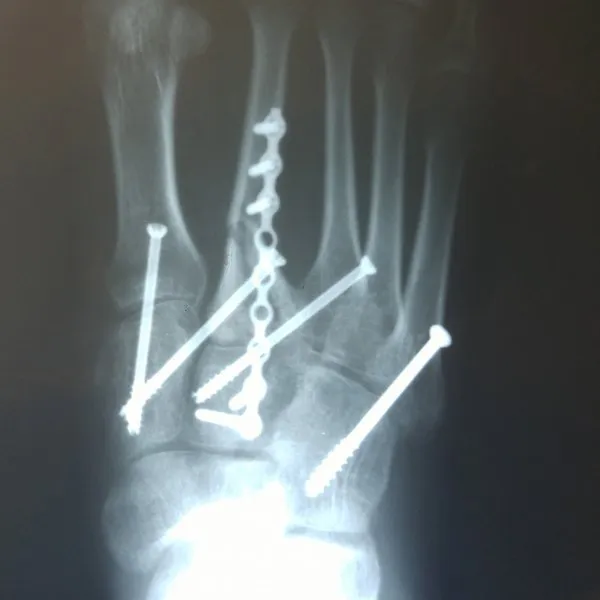

See What's Going on Inside Our Podiatrist's Office

With 32 years of experience, Dr. Daniel Brandwein DPM, PA, FACFAS is your trusted choice for podiatric care in the Pompano Beach, FL area. Take a look at the photos below to see what's happening inside our locally and family owned clinic. To find out how we can help with your foot care needs, please contact us today.